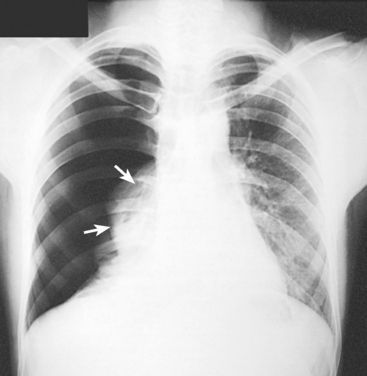

Structures shown: AP or PA projection obtained using the lateral decubitus position shows the change in fluid position and reveals any previously obscured pulmonary areas or, in the case of suspected pneumothorax, the presence of any free air (Figs. 10-62 to 10-64).

Fig. 10-62 AP projection, right lateral decubitus position, showing a fluid level (arrows) on the side that is down. Note the fluid in the lung fissure (arrowhead). Note correct marker placement, with the upper side of the patient indicated.